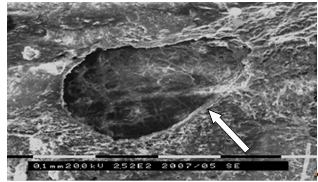

Второй этап эксперимента имел целью изучение влияния выбранного способа

коррекции выявленных ультраструктурных изменений костного матрикса в

эксперименте на биообъектах (10 баранах). На данном этапе, после нанесения

биообъектам огнестрельного перелома диафиза большеберцовой кости, проводилась

традиционная схема лечения огнестрельных переломов с добавлением в рацион

животных стронция ранелата. В последующем, после выведения животных из

эксперимента на 15-е, 30-е и 60-е сутки лечения, производился забор костных

образцов из зоны костного регенерата и их исследование.

. Исследования тонкой структуры костного матрикса области регенерата

методом сканирующей электронной микроскопии (10 образцов).